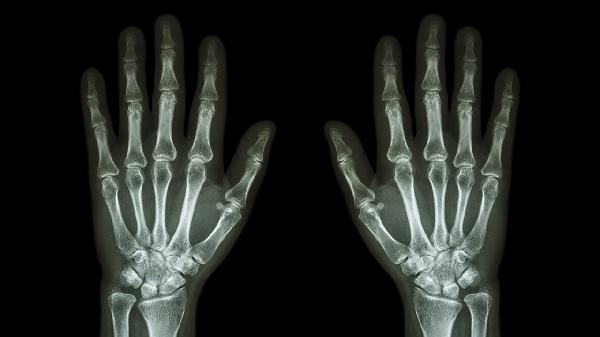

关节软骨退化引发的炎症反应常见于中老年人群,晨起僵硬感明显,X线可见关节间隙变窄。治疗需结合关节保护训练,严重时需注射透明质酸钠缓解症状。